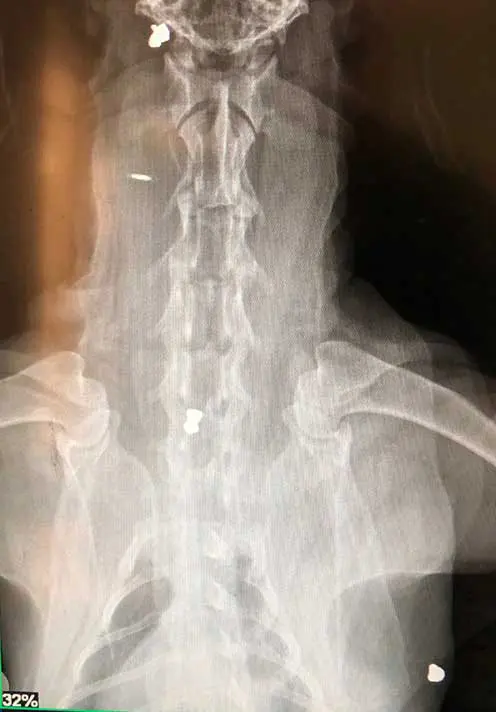

X-rays or radiographs are the most common piece of diagnostic equipment available in first opinion practice. X-rays are produced when electrons hit metal while travelling at high speed. This is achieved by an electric current being conducted through a cathode via a high voltage power source, which enables energy to be released into the x-ray tube, become attracted to the anode and when the energy particles strike the anode in the x-ray head, x-rays are produced (Palgrave, 2022).

Radiographs can identify injuries or disease processes within the body by visualising bones, organs and other soft tissue structures – anything from fractures and osteosarcomas to bladder stones, foreign bodies and gastric dilation volvulus.